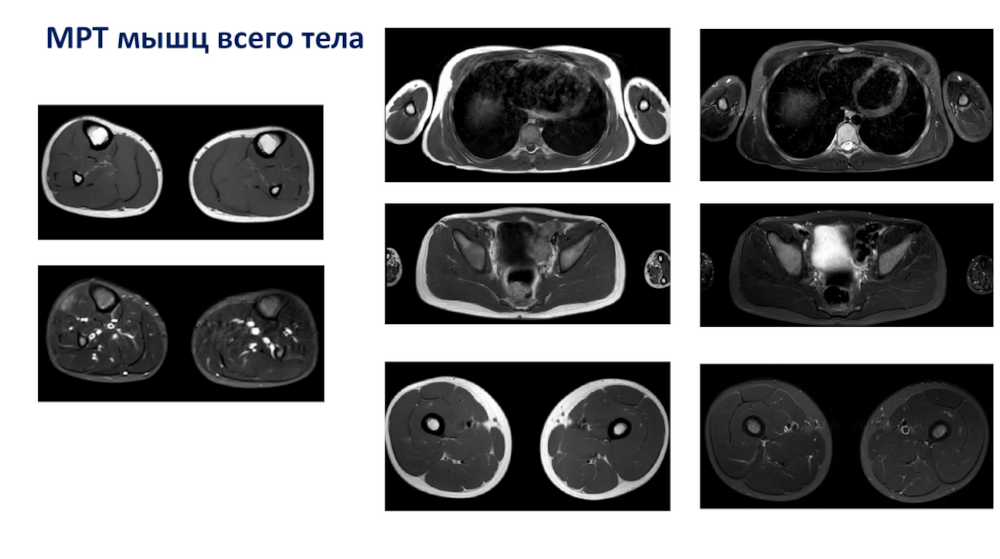

При миопатиях пациенту проводят МРТ мышц всего тела, и сотрудники МГНЦ им. Н.П. Бочкова решили проверить, что покажет МРТ у их пациентов. В частности, они проанализировали случаи заболеваний, связанных с дисфункцией тропомиозина. Это врожденные миопатии, по мере прогрессирования которых развиваются контрактуры суставов. У пациентов с заболеваниями этой группы на МРТ не было выявлено признаков фиброза или замещения мышц жировой тканью.